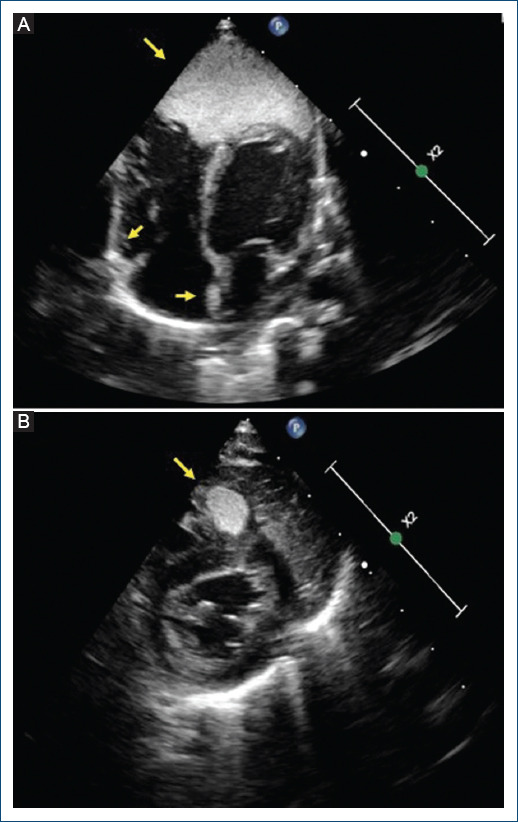

[Giant cardiac rhabdomyoma: an atypical cause of ST-segment elevation in the newborn].

{"title":"[Giant cardiac rhabdomyoma: an atypical cause of ST-segment elevation in the newborn].","authors":"Martín Negreira-Caamaño, Laura Acero-García de la Santa, Daniel Salvo-Chabuel, María Arántzazu-González-Marín","doi":"10.24875/ACM.23000195","DOIUrl":null,"url":null,"abstract":"","PeriodicalId":93885,"journal":{"name":"Archivos de cardiologia de Mexico","volume":" ","pages":"533-534"},"PeriodicalIF":0.0000,"publicationDate":"2024-07-18","publicationTypes":"Journal Article","fieldsOfStudy":null,"isOpenAccess":false,"openAccessPdf":"https://www.ncbi.nlm.nih.gov/pmc/articles/PMC12148531/pdf/","citationCount":"0","resultStr":null,"platform":"Semanticscholar","paperid":null,"PeriodicalName":"Archivos de cardiologia de Mexico","FirstCategoryId":"1085","ListUrlMain":"https://doi.org/10.24875/ACM.23000195","RegionNum":0,"RegionCategory":null,"ArticlePicture":[],"TitleCN":null,"AbstractTextCN":null,"PMCID":null,"EPubDate":"","PubModel":"","JCR":"","JCRName":"","Score":null,"Total":0}